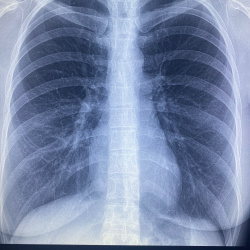

Молодая женщина. проф ФЛГ. Архива нет.